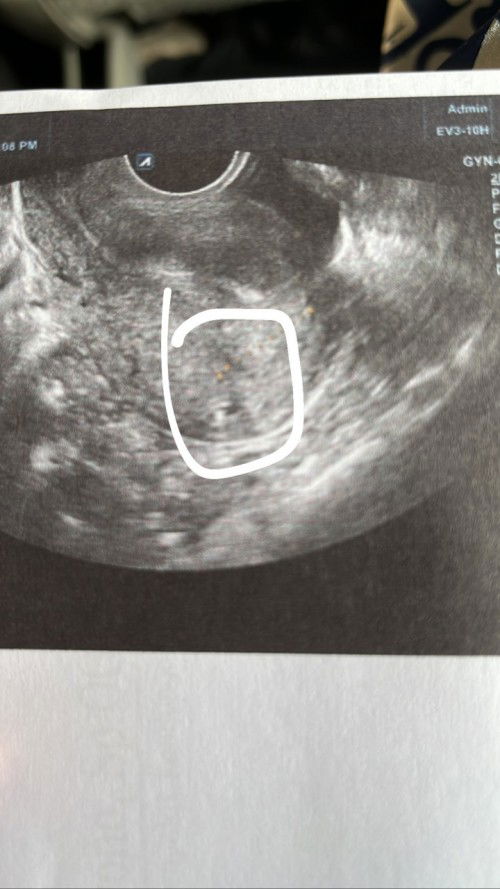

Mau tanya dong apakah ini sudah ada kantung janin nya

Apakah kantung janin sudah terlihat

ga tau bun ga kliatan dr foto doang. lha usg nya gmn?emg ga tanya dokternya

gak nanya kedokternya mmg? dokternya pas lagi usg diem bae ?